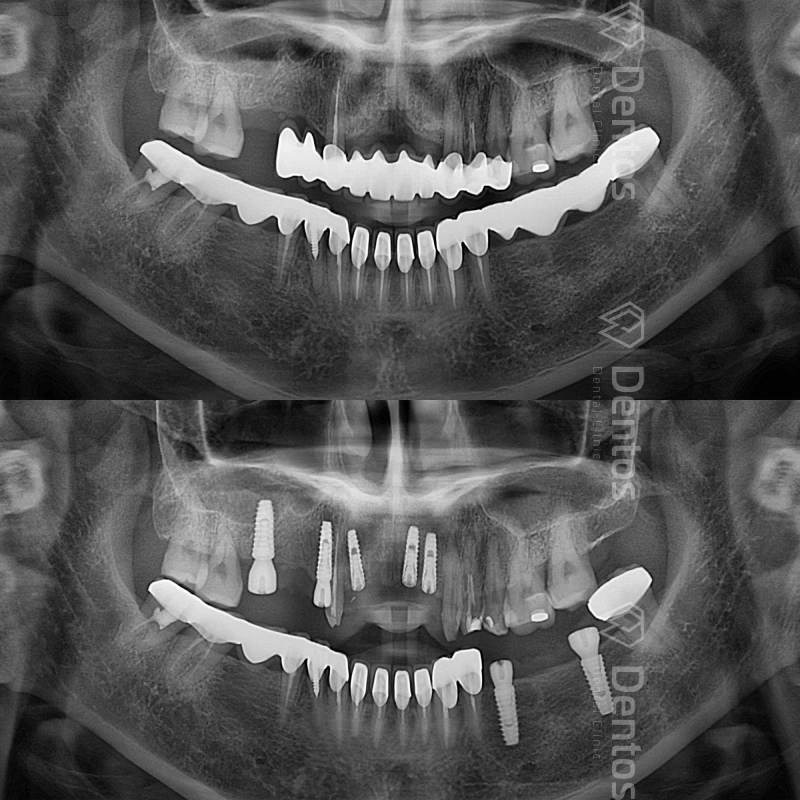

Dentos thực hiện thành công hàng ngàn ca răng toàn hàm và đơn lẻ.

Chụp phim CT Conebeam 3D - Kỹ thuật xuất phim 3 chiều của mô răng, mô mềm, xương hàm và ống thần kinh để đưa ra kế hoạch điều trị.

Tiến hành cấy ghép Implant vào bên trong xương hàm.

Chờ đợi Implant tích hợp với xương hàm (khoảng vài tháng).

Phục hình mão sứ hoàn thiện sau khi Implant đã ổn định.